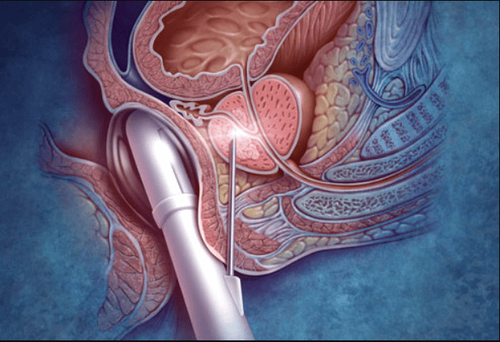

Ngoài ra siêu âm cũng có thể được sử dụng trong một số các thủ thuật khác mà điển hình là sinh thiết tế bào. Đầu dò siêu âm sẽ được gắn vào đầu ống nội soi để giúp xác định và lấy chính xác các tế bào tại nơi cần sinh thiết.

- Người bệnh trước khi siêu âm sẽ được yêu cầu cởi bỏ quần áo và trang sức đeo trên người hay ít nhất là để lộ ra khu vực cần siêu âm. Một loại gel sẽ được thoa đều vào khu vực đó

- Đầu dò sẽ được các kỹ thuật viên nhẹ nhàng di chuyển trên da. Khi các đầu dò tiếp xúc với da, chúng gửi đi xung sóng âm tần số cao, sóng âm tiếp xúc với các cơ quan và nội tạng trong cơ thể rồi phản xạ ngược trở lại, các đầu dò có nhiệm vụ thu nhận hết âm phản xạ này, gửi cho bộ xử lý trung tâm. Tại đây, dựa vào cường độ sóng, thời gian âm phản xạ trở lại máy sẽ phân tích và đưa ra hình ảnh của các cơ quan, nội tạng đó được hiển thị trên màn hình. Đối với siêu âm Doppler, sự chuyển động của các tế bào máu gây ra sự thay đổi của cường độ sóng phản xạ qua đó hiển thị hình ảnh dòng máu chảy trong lòng mạch